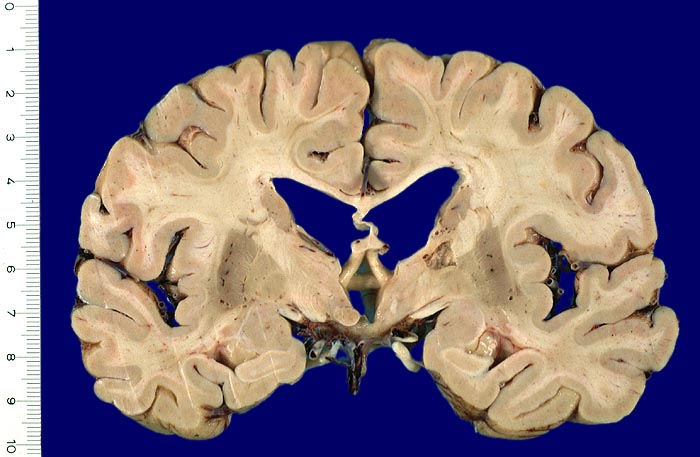

PathoPic – image database / PathoPic ID 4005 - Lakunärer Infarkt

Lakunärer Infarkt

Unregelmässig begrenzter Hohlraum (lakunärer Infarkt) im Bereich der Capsula interna. Die Seitenventrikel sind erweitert.

Lakunäre Infarkte im Bereich des Linsenkerns, des Thalamus, der Capsula interna, der tiefen weissen Substanz, des Nucleus caudatus und der Pons sind weniger als 1.5cm gross und oft Folge einer hypertensiven Enzephalopathie (Atherosklerose der Arteriolen, welche Basalganglien, weisse Substanz und Hirnstamm versorgen). Das Vorliegen multipler Lakunen wird als Status lacunaris bezeichnet. Die Infarkte sind je nach Lokalisation symptomatisch oder asymptomatisch.